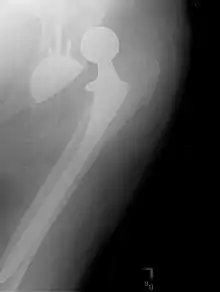

Prothèse totale de hanche

Une prothèse totale de hanche (PTH) est un dispositif articulaire interne qui vise à remplacer l'articulation de la hanche et lui permettre un fonctionnement quasi normal, en tout cas permettant la marche.

De nouveaux couples de friction apparaissent. Le couple céramique-céramique prend son essor. La tête fémorale est fixée sur un cône morse, le cotyle est enchâssé dans une coque « metal back ». Un autre couple réapparaît depuis quelques années : le métal-métal. En effet grâce aux progrès d’usinage l’usure de ce couple est maintenant très faible.